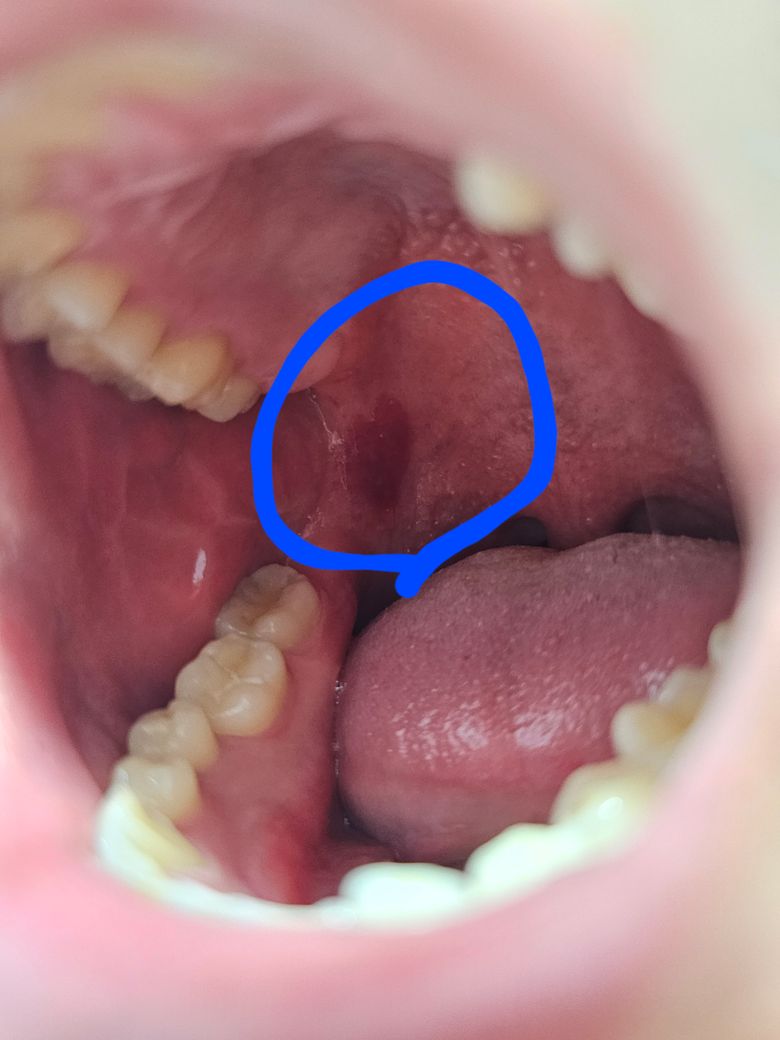

집에서 술한잔하고 있던중 입안에 물집같은것이 잡히더군요 신경 쓰여서 터트렸는데 당혹스럽게도 제법 많은양의 피가 나왔습니다. 현재는 상처처럼 빨갛게 남아있고 물이나 음식을 섭취할때 쓰라린 정도인데 괜찮은걸까요?

깨물려서 물집이 생긴 것으로 보이며 이것은 흐트려도 아무른 문제 되지 않습니다. 그냥두면 됩니다. 며칠 지나면 저절로 아뭅니다.

해당부분을 씹어서 단순히 혈종이 생겼을 수 있으며 재발하지 않는다면 괜찮을 것 같습니다.

뜨거운 음식등에 잇몸에 수포가 생긴거 같습니다. 큰 문제가 잇는건 아니니 최대한 자극이 가지 않도록 해주시면될것같습니다.

점막이 과도한 외부 자극이 가해지면 내부에 출혈이 되면서 혈액이 찰수 있습니다.

혈액종이라고 하는데 크게 문제가 되지는 않습니다.

같은 증상이 자주 발생되거나 한다면 치과에서 자세한 확인을 위해 진료를 받아 보는것이 좋습니다.

구내 혈종이 터진게 아닐까 싶습니다. 감염 가능성이 있기 때문에 이비인후과 또는 치과가서 소독 처치를 받는 것을 추천드립니다.